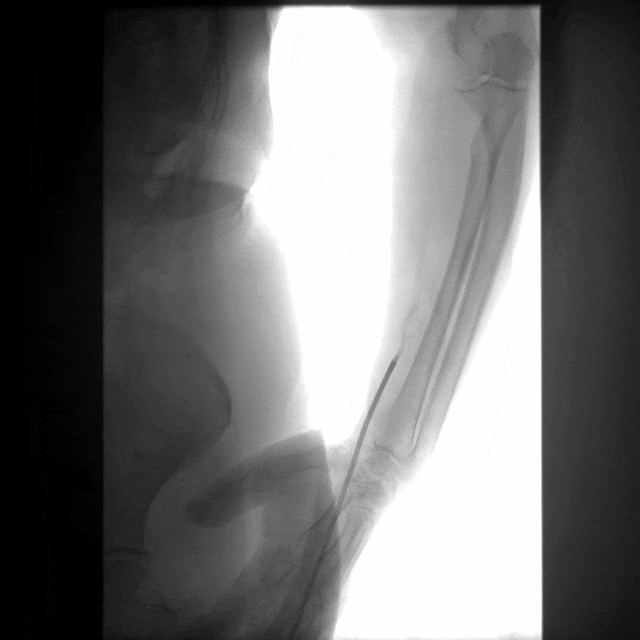

外院造影:

右肾动脉重度狭窄

2.导管配合0.035导丝进入腹主动脉下端,造影示:腹主动脉走形迂曲,血流通畅,右肾动脉主干起始段重度狭窄>90%,远端及分支显影浅淡。